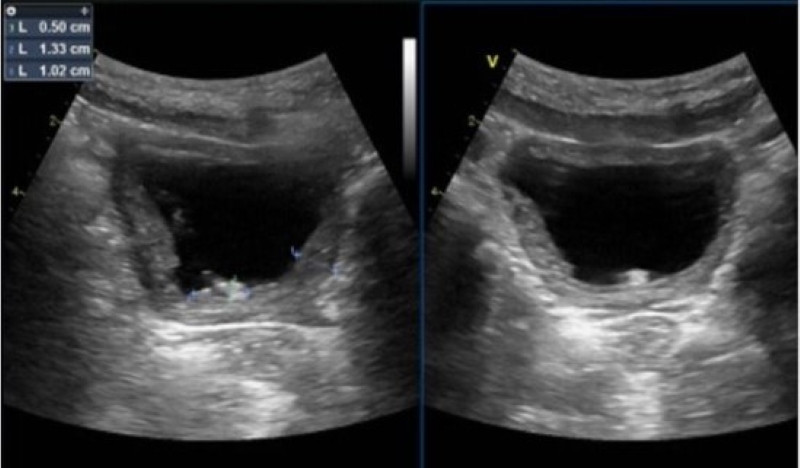

| Hình ảnh siêu âm của bệnh nhi phát hiện sỏi bàng quang. Ảnh PKCC |

Sau đó, trẻ được bác sĩ chỉ định thực hiện các kỹ thuật cận lâm sàng phục vụ chẩn đoán. Trong đó, kết quả xét nghiệm cho thấy bạch cầu, hồng cầu tăng, chỉ số Nitrit dương tính. Đặc biệt, trên hình ảnh siêu âm phát hiện thành bàng quang dày 10.2mm, trong có đám sỏi kích thước 13x5mm. Bác sĩ kết luận tình trạng của trẻ là viêm bàng quang cấp trên nền bàng quang.